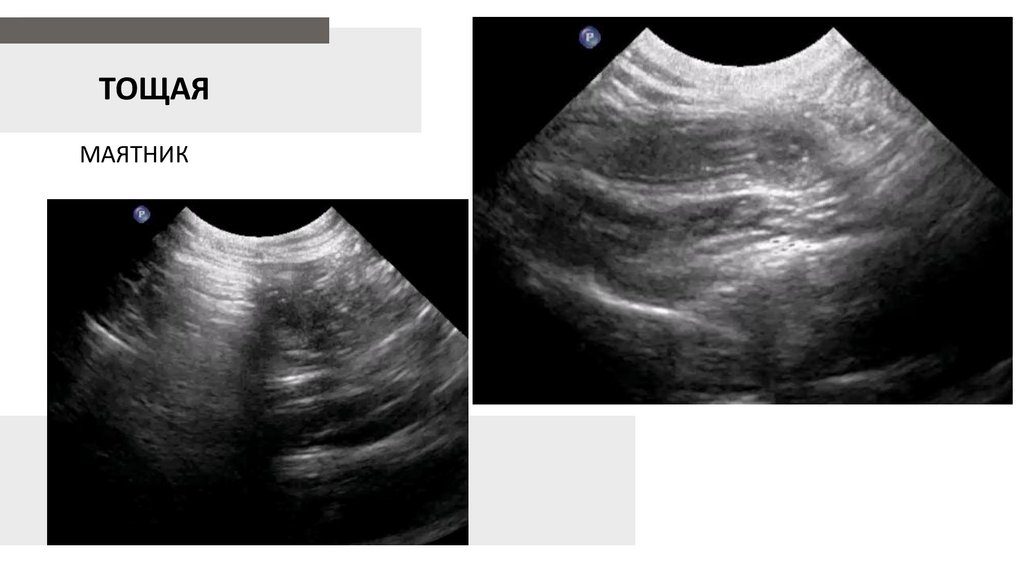

ТОЩАЯ

МАЯТНИК

21.